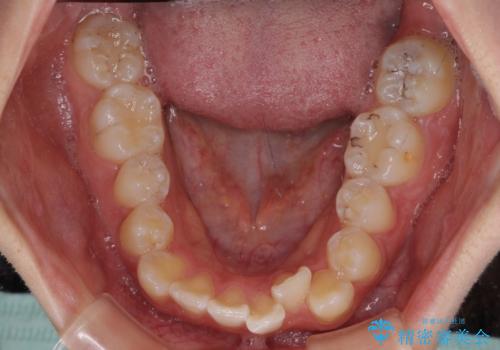

- 前歯のデコボコと八重歯を気にして来院された患者様です。

インビザラインでの治療を希望されていましたが、前歯のクロスバイトや下顎小臼歯の捻転が認められたため、インビザライン単独で治療を行うよりも、ワイヤー装置を併用した方が、治療期間の短縮やトラブル回避できると判断し、ワイヤー装置を併用することとしました。

まずはワイヤー装置により前歯のクロスバイトと下顎小臼歯の捻転を改善し、その後インビザラインにより全体を整える矯正治療を行うこととしました。

前歯のクロスバイトは、インビザラインでの改善中に前歯に過剰な力がかかり、歯髄壊死や歯肉退縮を引き起こすことがあります。また下顎小臼歯は寸胴型のため、捻転を排除することが難しいことが知られています。